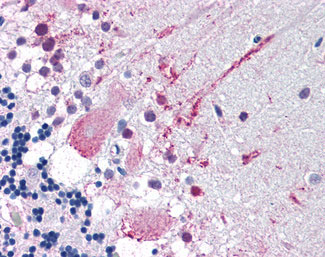

Anti-MRGPRF antibody AMM06475G IHC of human brain, cerebellum. |